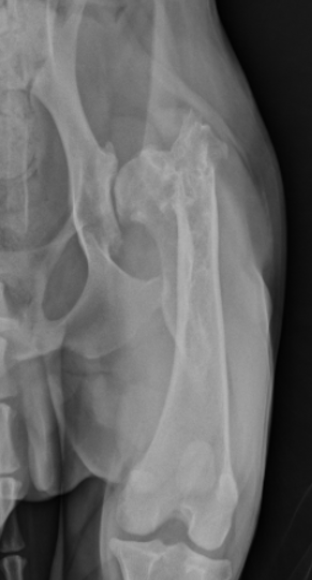

What is shown in this radiograph?

widening of humero-ulnar joint space due to premature distal ulnar physis closure